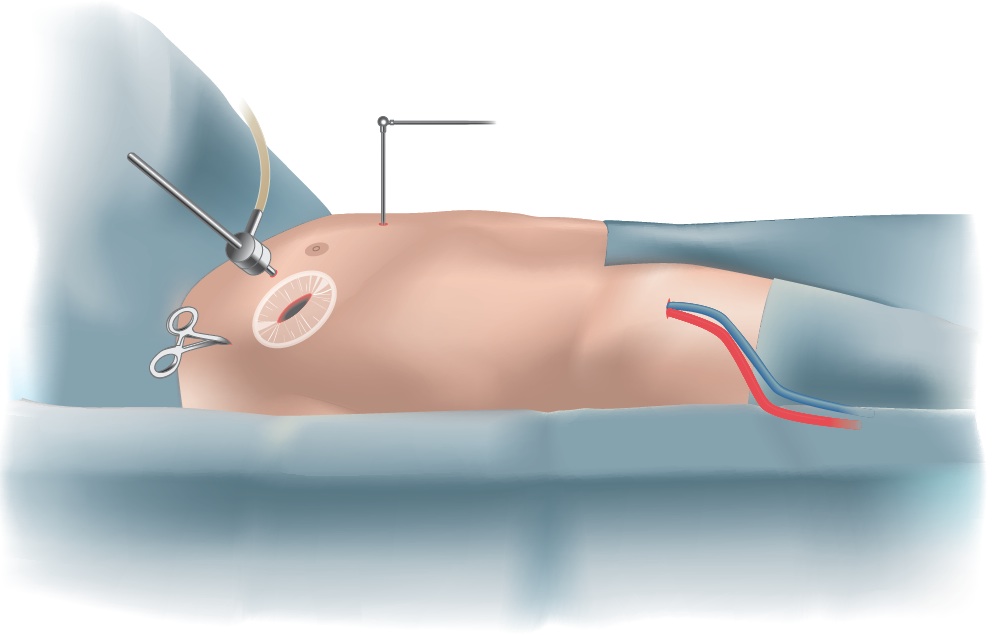

The surgery is performed through the small space between the ribs. The heart-lung machine is inserted via a small incision in the groin, allowing the heart to be stopped for the sewing of the patch. A soft retractor is inserted, which gently opens the narrow space between the ribs, enabling the surgeon to insert the specialized minimally invasive instruments. An endoscope, ideally with a 3D camera, is inserted that will provide a high-resolution image of the heart and the ASD.

Using this technique, the stability of the chest is fully preserved, patients recover more quickly, and the minimal scar will be barely visible after the patient recovers.

Fig. 4 - Surgical setup